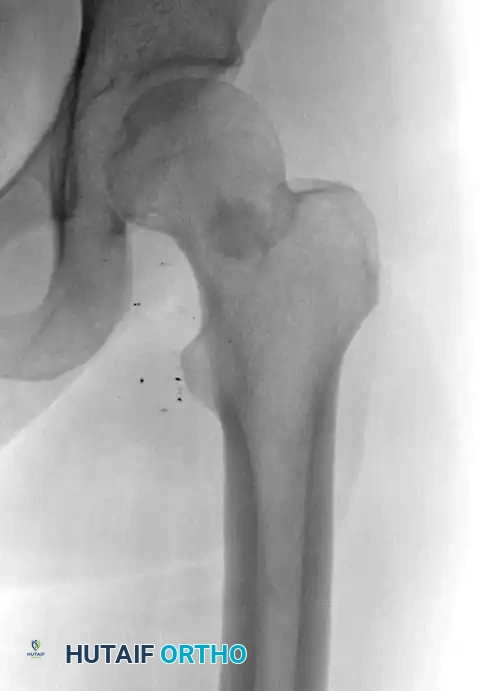

Radiograph demonstrating a pedunculated osteochondroma of the proximal femur.

MRI confirming that the cortex and medullary canal of the lesion are in direct continuity with the host bone.